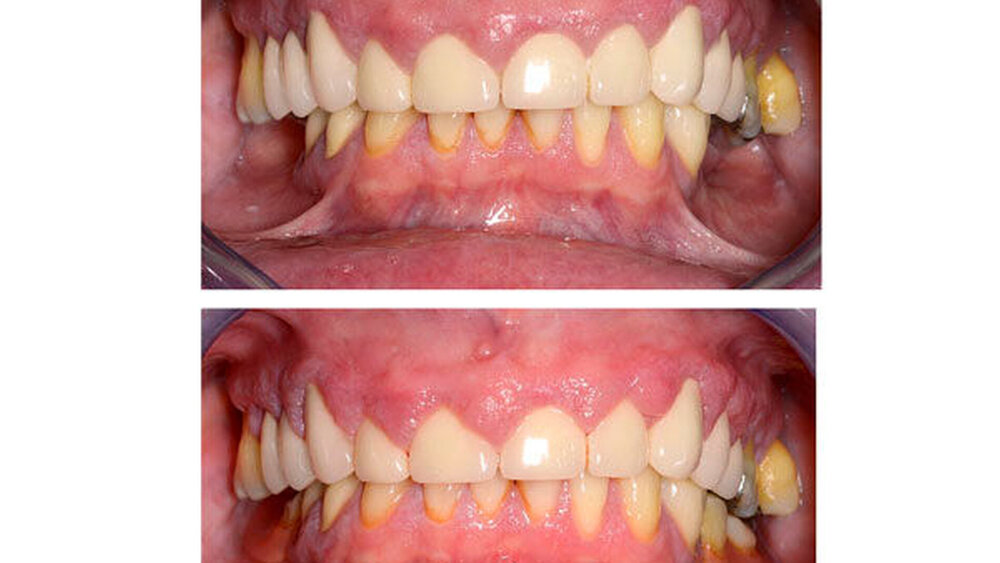

Anamnese: Die 53-jährige Frau stellte sich im Januar 2015 in der Poliklinik für Parodontologie des Universitätsklinikums Dresden vor. Sie war von ihrer Hauszahnärztin mit der Bitte um Diagnostik und Therapie der gingivalen Größenzunahmen (Abbildungen 1a bis 1e) überwiesen worden. Die Patientin gab an, dass die Vergrößerung der Gingiva vor ungefähr einem Jahr begonnen habe und diese sie mittlerweile in ihrer häuslichen Mundhygiene einschränke. Die Benutzung von Hilfsmitteln zur Interdentalraumpflege sei nicht mehr möglich und die Gingiva blute seitdem häufig. Den Kaukomfort ihres 2009 angefertigten Zahnersatzes empfand sie als gut. Als Grund für die multiplen endodontischen Therapien und die Überkronungen an den Zähnen 15, 13 bis 22 sowie 24 und 25 gab die Patientin starke Abrasionen an. Seit dem Auftreten der Gingivawucherungen ergänzte sie auf Anraten ihrer Hauszahnärztin die häusliche Mundhygiene einmal täglich mit Chlorhexidingel, 1-prozentig.

Befund: Bei der klinischen Untersuchung zeigten sich vestibulär und oral im Bereich der Papillen und der befestigten Gingiva generalisierte Gingivawucherungen im Oberkiefer (OK) und im Unterkiefer (UK). Die Interdentalräume waren aufgrund der Gingivawucherungen nicht für Hygienehilfsmittel durchgängig. Der Parodontale Screeningindex (PSI) wies im OK die Codes 3/3/4, im UK die Codes 3/1/3 auf. Der daraufhin erhobene Parodontalstatus (Abbildung 2) zeigte im OK Sondierungstiefen bis 7 mm mit Furkationsbeteiligungen Grad I (Zähne 16, 26, 27). Im UK betrugen die Sondierungstiefen bis zu 4 mm. Die Zahnbeweglichkeit an den Zähnen 16, 26 (Grad I) und 27 (Grad II) war erhöht.

Sechs Wochen nach Deep Scaling und Root Planing erfolgte eine zweite Reevaluation mit Befunderhebung [MacNeil RL et al., 1999]. Erhöhte Sondierungstiefen lagen nur noch an den Zähnen 27 (5 mm) und 34 (4 mm) vor (Abbildung 4). Die Gingivawucherungen hatten sich vollständig zurückgebildet (Abbildungen 5a bis 5e). Die Plaque- und Blutungsindizes waren niedrig und stabil (20 Prozent). Abschließend wurde eine PZR zusammen mit einer subgingivalen Reinigung an den Zähnen 27 und 34 durchgeführt. Die Prognose der Zähne mit Ausnahme des Zahns 27 ist weiter als sicher einzustufen. Zahn 27 bleibt kritisch. Dies ist durch den Attachmentverlust von 10 mm mesial und den Lockerungsgrad II begründet. Aufgrund der kompromittierenden parodontalen Situation und der eingeschränkten prothetischen Wertigkeit könnte bei Beschwerden an Zahn 27 neben einer chirurgischen Taschenelimination auch eine Extraktion erwogen werden. Die bisherige prothetische Versorgung könnte dann im Konzept einer verkürzten Zahnreihe belassen werden [Fueki K et al., 2015; Levey C et al. 2015]. Da die Patientin vorerst keine weitere Therapie an Zahn 27 wünschte, musste an dieser Stelle von einer chirurgischen Taschenelimination abgesehen und der Zahn belassen werden.